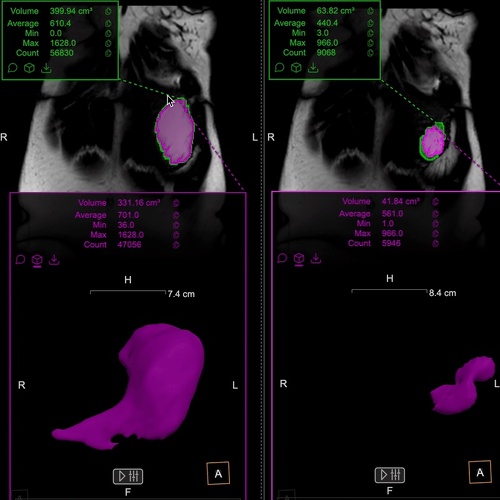

Understanding gastric physiology with MRI

MRI provides a non-invasive way to assess gastric emptying, accommodation, and motility. Validated against scintigraphy, barostat, and manometry, it offers unique insights into gastric function and supports both clinical care and research.